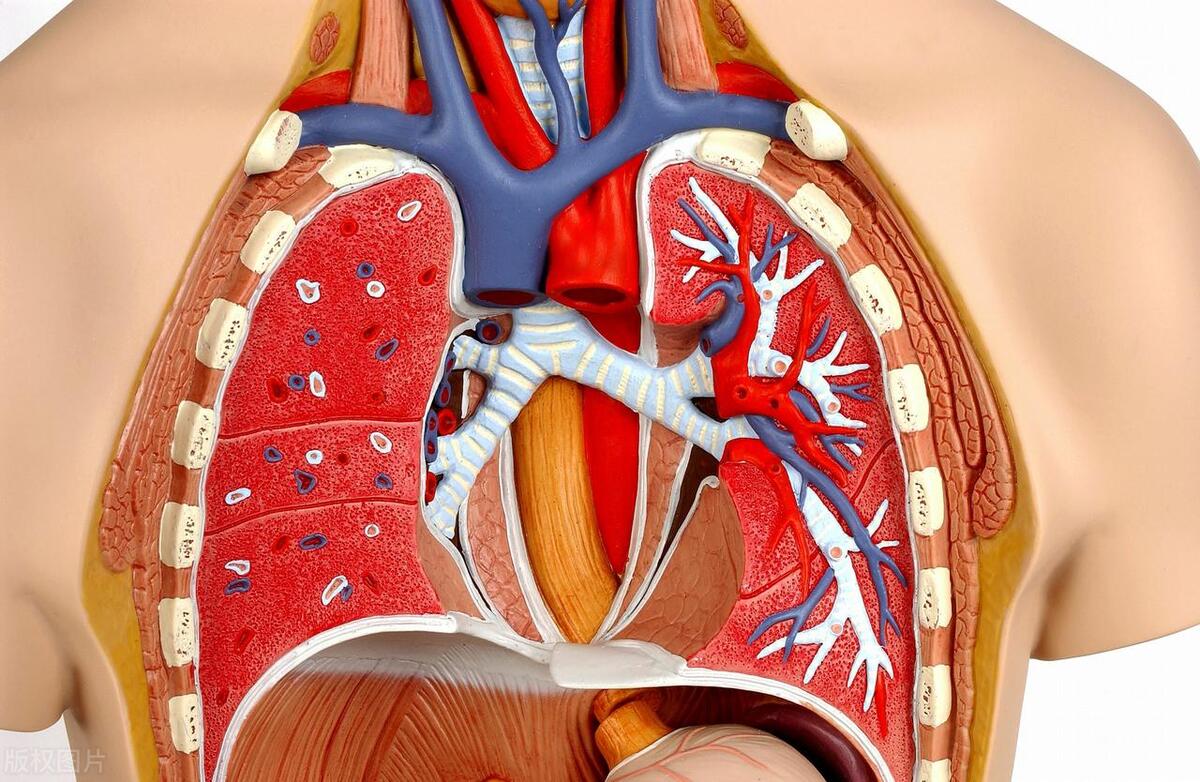

肺动脉栓塞(pulmonary embolism,PE)是由血栓脱落至到人体肺部肺动脉主干或其分支从而导致的,静脉血栓栓塞症(venous thromboem bolism,VTE)是 深静脉血栓DVT 与 PE 的合称。发生创 伤的病人最容易出现的并发症就是 DVT。